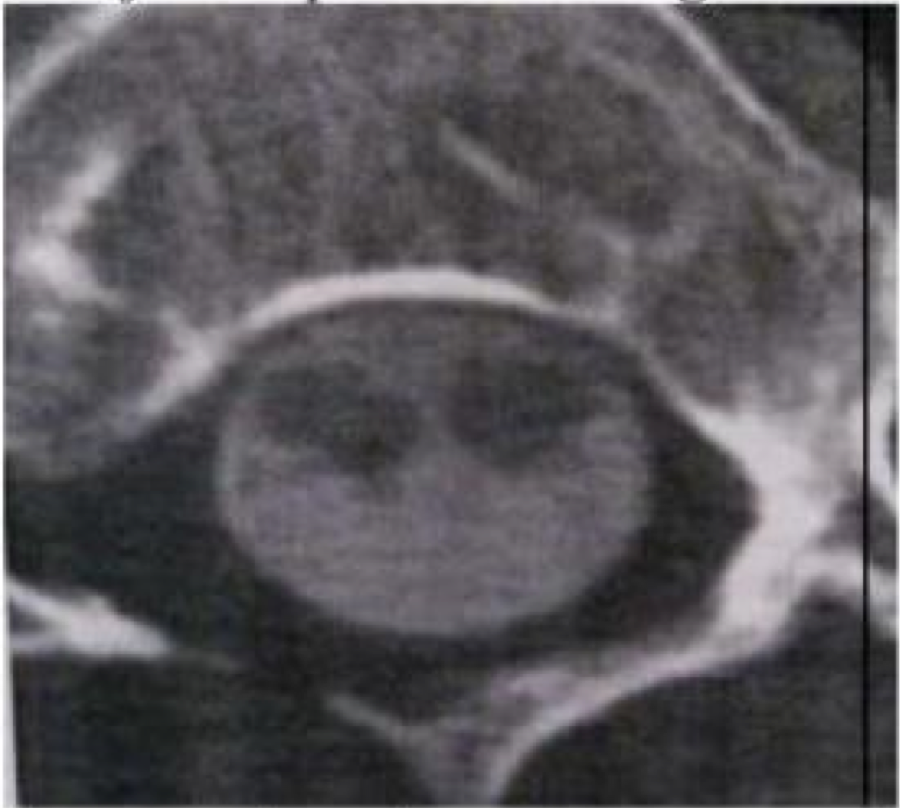

Mekanisme cedera pada fracture di bawah ini (CT Scan Aksial)

A. Retak Dislokasi

B. Kompresi Aksial

C. Distraksi Fleksi

D. Hiperekstensi

E. semuanya salah

B